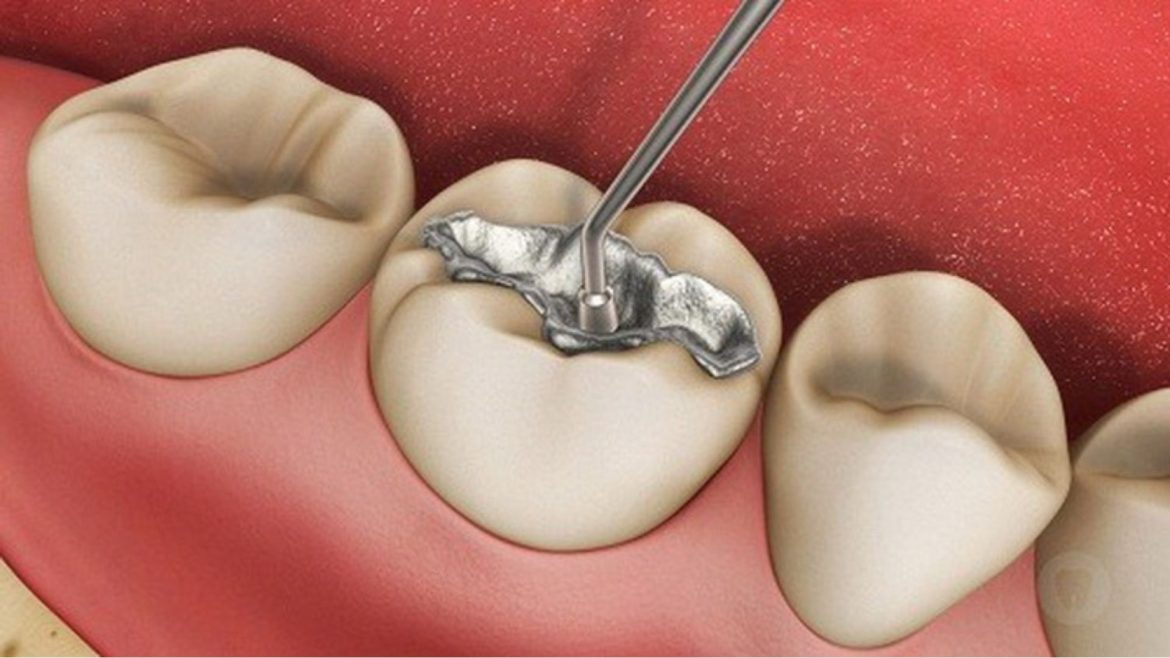

Trám răng thẩm mỹ không chỉ hữu ích trong việc khắc phục lại tính hoàn thiện cho răng bị mẻ mà còn vô cùng hữu ích trong việc điều trị răng sâu hay răng bị mẻ. Mặc dù đây là …